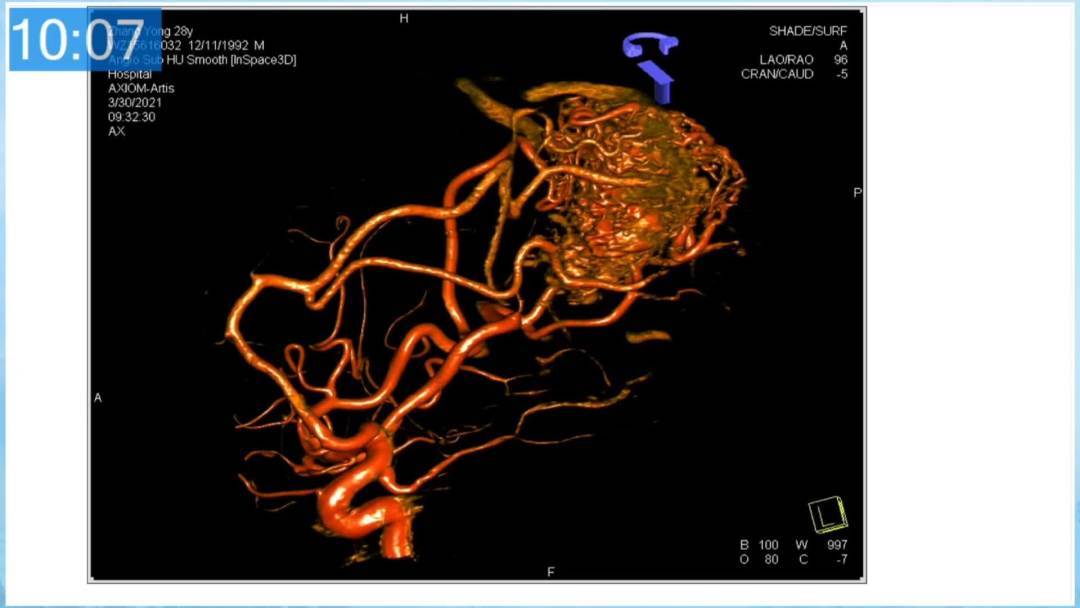

本期为大家特别分享:空军军医大学唐都医院邓剑平教授的精彩会议内容《颅内动静脉畸形的复合手术治疗》,欢迎大家阅读和分享!